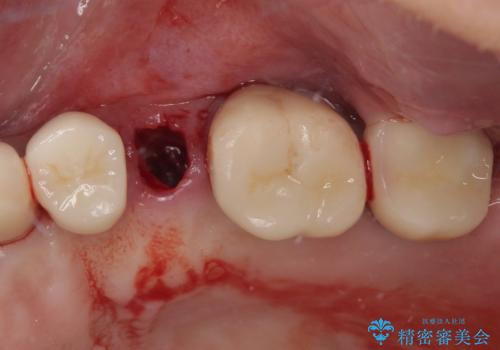

破折によりクラウンの外れてしまった奥歯 抜歯即時埋入で短期間インプラント治療

- 奥歯に装着していたクラウンが外れてしまったとのことで来院された患者様です。

診察したところ、歯根に破折線が確認され抜歯が必要な状態でした。

歯肉や歯槽骨の状態は良好であったため、抜歯即時埋入インプラントによる補綴治療を行うこととしました。